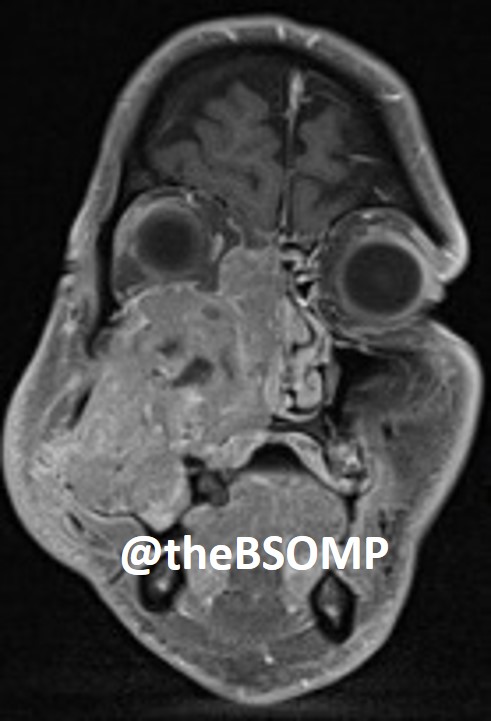

@theBSOMP Case of the Month for Jan/Feb 2024 is now live.

Visit bsomp.org.uk/cotm for details.

Case credit-@histopathhannah @M0llieclark